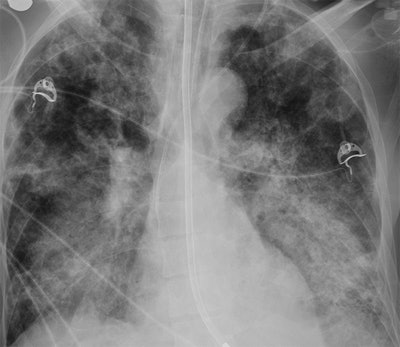

A new study of Saudi Arabian patients with Middle East respiratory syndrome (MERS) found that a simple method of scoring pathology on lung radiographs can be used to predict which patients are at risk of dying, according to a Web-exclusive article in the American Journal of Roentgenology.

In the study, a multicenter group from hospitals in Saudi Arabia, the U.S., Qatar, and the United Arab Emirates applied a protocol in which three radiologists scored chest radiographs based on the development of MERS lesions over time in a group of 55 patients. They found that the scores correctly predicted which patients would die -- in fact, it was the only factor that showed a statistically significant relationship to mortality, even when conditions such as diabetes mellitus and congestive heart failure were considered.

The first step of the protocol is to divide each lung into three zones, for a total of six zones across both lungs. Then, radiologists assign scores to rate the involvement of disease in each zone, ranging from 0 (normal) to 4 (total involvement of the zone). Finally, the scores are summed to indicate the extent of pathology -- a score of 24 would mean complete involvement of all lung zones with disease.

Three radiologists first scored the radiographs at the initial presentation of the subjects, repeating the process at the time of peak radiographic deterioration. They found that the mean score of the subjects who died increased from 1.4 at initial presentation to 13 at the time of peak deterioration (p = 0.001). Death rates were highest in those with the most severe disease progression.

Which radiographic characteristics were most common in the individuals who died? Das and colleagues identified several, including the following:

- Higher incidence of disease involvement in the right lower zone, right middle zone, and left middle zone

- Pleural effusion, pneumothorax, a chest radiographic score of 13 or higher, and worse deterioration, especially when associated with other clinical factors

"Pleural effusion, pneumothorax, a higher chest radiographic score, and a high number of medical comorbidities in MERS-CoV-infected patients were indicative of a poor prognosis and high short-term mortality," the authors concluded.